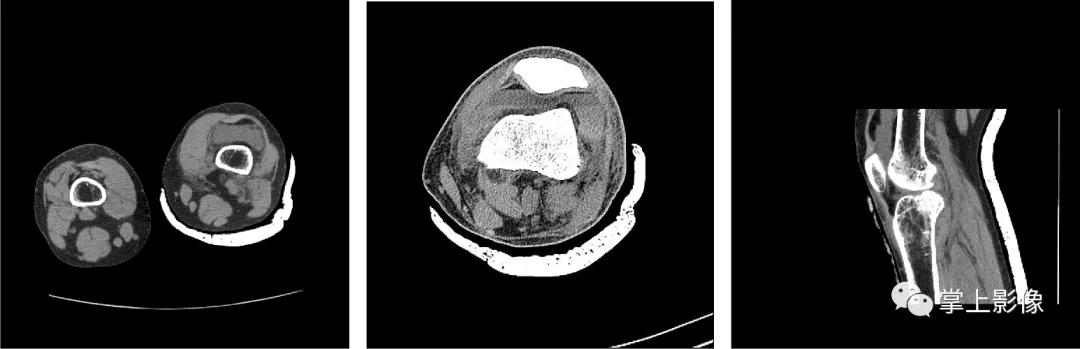

图1 、2为同一患者胫骨平台骨折合并积脂血症不同界面的 CT 表现,液平上方为脂肪,下方为关节内出血,可见单液-液平面征。图 3 为髌上囊积脂血征,胫骨平台骨折合并腓骨小头骨折。图 4 为 1 例隐匿性骨折患者,男,48 岁,车祸外伤,左膝关节活动受限,普通 X 线检查提示髌上囊内密度升高,常规平扫见脂液平面,经薄层重建充分显示左髌骨外侧缘撕脱骨折

- 关节内骨折之后从撕裂处骨膜组织或者是骨髓腔内溢出的血液与脂肪同时进入到关节内囊中,同时因关节软骨及滑膜释放的一种酶能发挥阻止血凝块形成的作用,导致进入关节囊内的血液无法凝结,并与脂肪分离,密度小的脂肪浮于上层,而密度大的血液沉于下层,构成脂-血平面。这也是创伤性关节积脂血症患者在接受影像学诊断中最重要也最具特征性的表现,也是单液-液平面形成的原因